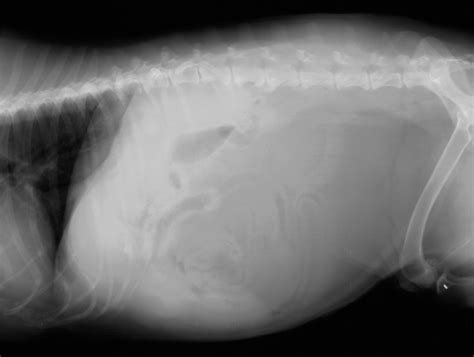

• picture of lipoma on stomach

• lipoma abdomen pictures